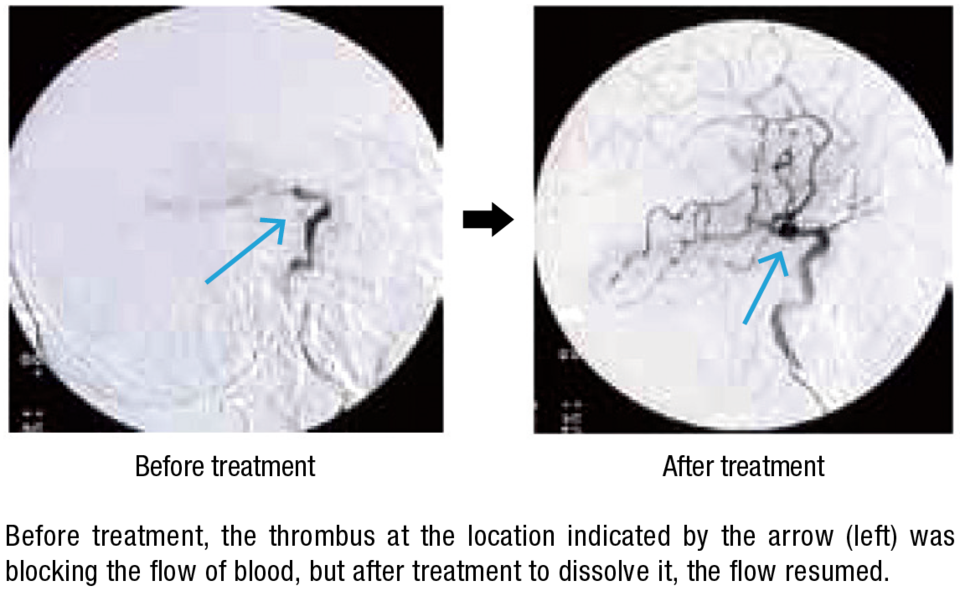

Hamamatsu Photonics has also developed many world-class products in the field of lasers, in which it started R&D activities in the 1990s. Recently it became the first in the world to develop a laser thrombolysis technology for treatment of cerebral thrombi—blood clots in the brain that cause strokes—which works as follows: A catheter encasing an optical fiber is inserted via a femoral artery and extended to the location of the thrombus, and a green laser beam at a wavelength of 532 nanometers is directed at the site. At this wavelength, the beam is not absorbed by the blood vessel wall but affects only the thrombus, which it dissolves with almost no risk of damage to the blood vessel walls. Since the tip of the catheter is thin, with a diameter of only 0.8 millimeters, and flexible, it can be used for treatment in blood vessels of around 1 mm in diameter, which are hard to treat with existing devices for suction-purpose catheterization. In this way it offers hopes for expanding the scope of cases that can be treated.

Hamamatsu Photonics has been conducting its research in collaboration with a local hospital and Hamamatsu University School of Medicine. Dr. Hiroyuki Okada, who is responsible for laser thrombolysis R&D at the company’s Central Research Laboratory, explains, “We had a hard time reconciling the different mind-sets of the medical treatment staff and the engineers.” The engineers wanted to create a device allowing fine-tuning of irradiation times, power, and other settings, while the medical staff wanted a simple-to-operate device that would let them concentrate on treatment. He says, “We put the wishes of the medical staff first and made adjustments, such as minimizing the number of operating buttons, while aiming for high reliability.” The effectiveness and safety of laser thrombolysis technology has been confirmed in experiments on animals, and it is planned to start clinical tests on humans this spring; the aim is to create a product for practical use in five years.